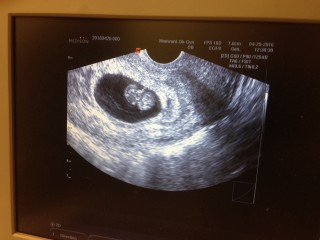

前日に少量の出血がありとても不安で、一週間後の検診まで待てずに病院に行ってきました。先生からも大丈夫とのお墨付きを頂き、安堵。一週間前は5.1mmで平均より小さく不安でしたが、今日は19.3mm。一週間で約1.5cmも大きくなっており、かなりびっくりしました。

茶オリが出て腹痛もあったので急遽診察してもらいました(;_;) 8週目のときは10mm程だったので小さめで心配でしたが、6日で19mmと9mmも大きくなっていて安心しました。 クリオネみたいで可愛すぎます。エコー写真何回も見ちゃいます! 来週でやっと予定日が決まるそうです。 これからが楽しみで仕方ありません! 頑張ってすくすく育ってね。